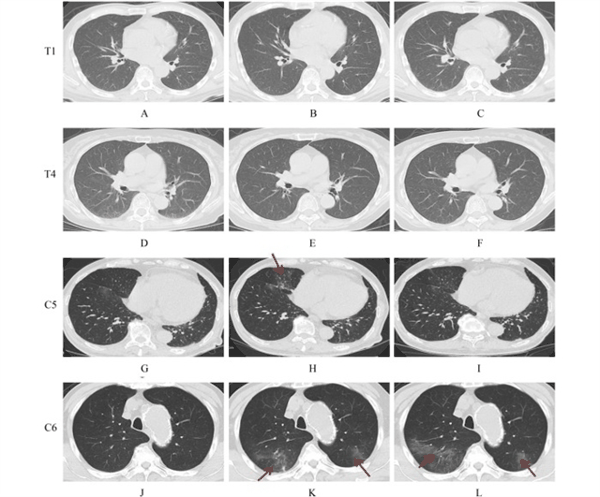

本研究共招募了2022年4月3日至5月30日期间确诊的13名血液透析患者,通过交互式响应技术系统将其随机分为治疗组(6人)和对照组(7人)(图1)。治疗组患者在基础治疗(包括中药、营养支持和吸氧)的基础上,接受每日一次口服150毫克奈玛特韦联合100毫克利托那韦治疗,持续5天;对照组仅接受基础治疗。通过动态监测患者的实验室参数发现,两组患者的白细胞计数在治疗期间未出现明显变化,但治疗组淋巴细胞水平呈现上升趋势(图2)。值得注意的是,治疗组在第8天的淋巴细胞和嗜酸性粒细胞绝对值较第1天显著升高,D-二聚体水平则呈现下降趋势,而对照组未观察到类似变化(图3)。在病毒清除方面,治疗组83.3%的患者在22天内实现核酸转阴,对照组这一比例为57.1%,尽管两组在转阴时间上未达到统计学显著差异,但治疗组在第8天的病毒载量显著低于对照组。胸部计算机断层扫描影像显示,对照组中有4名患者发展为中度肺炎,表现为肺部出现斑片状磨玻璃影,而治疗组患者未观察到病情进展(图4)。

图4 治疗组(T1,A–C;T4,D–F)与对照组(C5,G–I;C6,J–L)患者的胸部CT图像